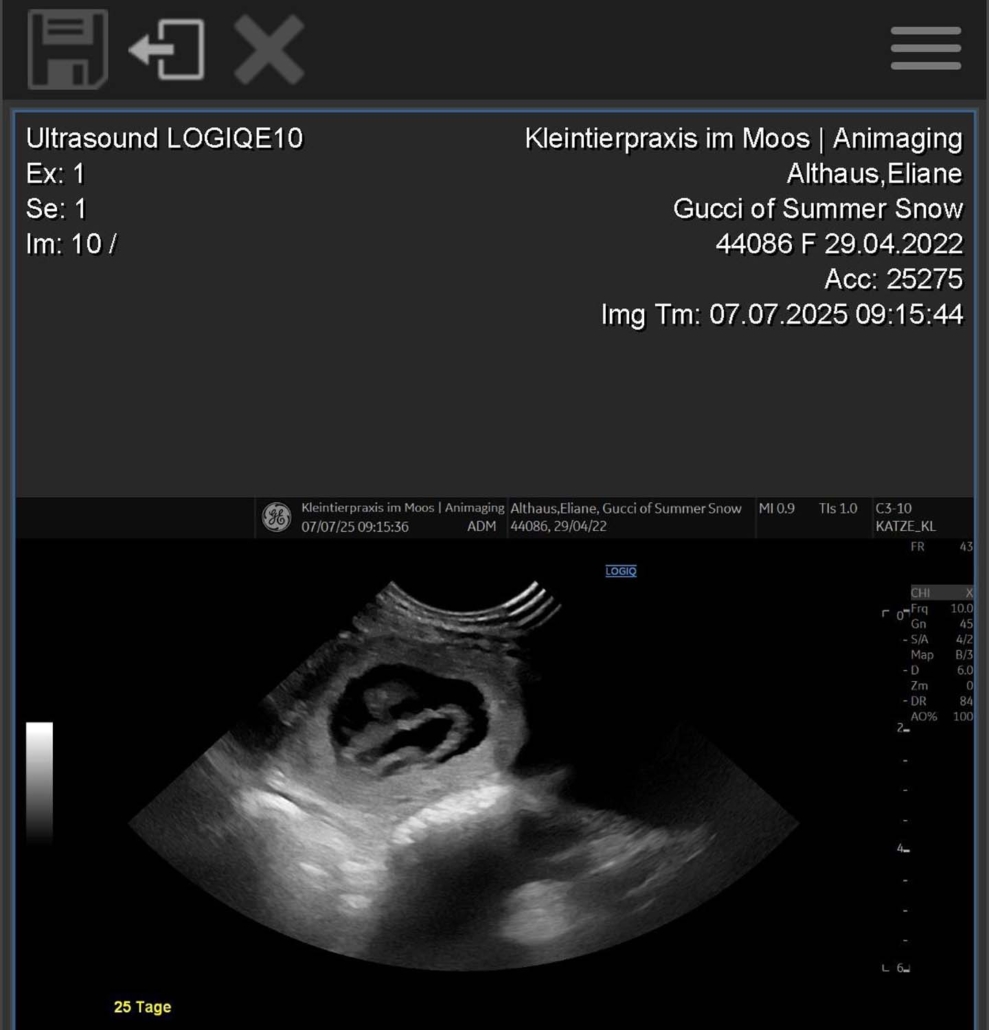

Gucci of Summer Snow | Geboren am 29.04.2022

Gucci ist trächtig – und wir freuen uns riesig auf Mitte August! Auf dem Röntgenbild sind vier kleine Parson Russell Terrier-Welpen zu erkennen! 🐶🐶🐶🐶